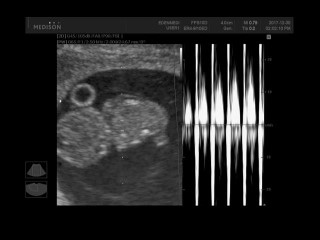

8주 5일_ 2017.12.30 젤리곰 헬롱이와의 만남

8주 5일_ 2017.12.30 젤리곰 헬롱이와의 만남 일주일이 지났지만 작년 12월 우리 헬롱이의 젤리곰 모습을 ...